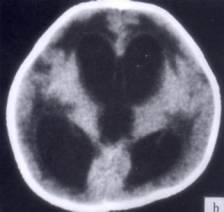

问题 病历摘要:??患者女性,10岁。结核性脑膜炎愈后8月,头痛伴恶心呕吐1周,并渐加重。体检:神清,精神差,反应迟钝,双眼底视神经乳头水肿,双眼外展差,余未见明显异常。 该患者宜采用下列哪种治疗手段?

选项 A.侧脑室-枕大池分流术 B.终板造瘘术 C.侧脑室-腹腔分流术 D.侧脑室-右心房分流术 E.侧脑室-颈静脉分流术 F.腰椎蛛网膜下腔-腹腔分流术 G.脉络丛烧灼术

答案 C